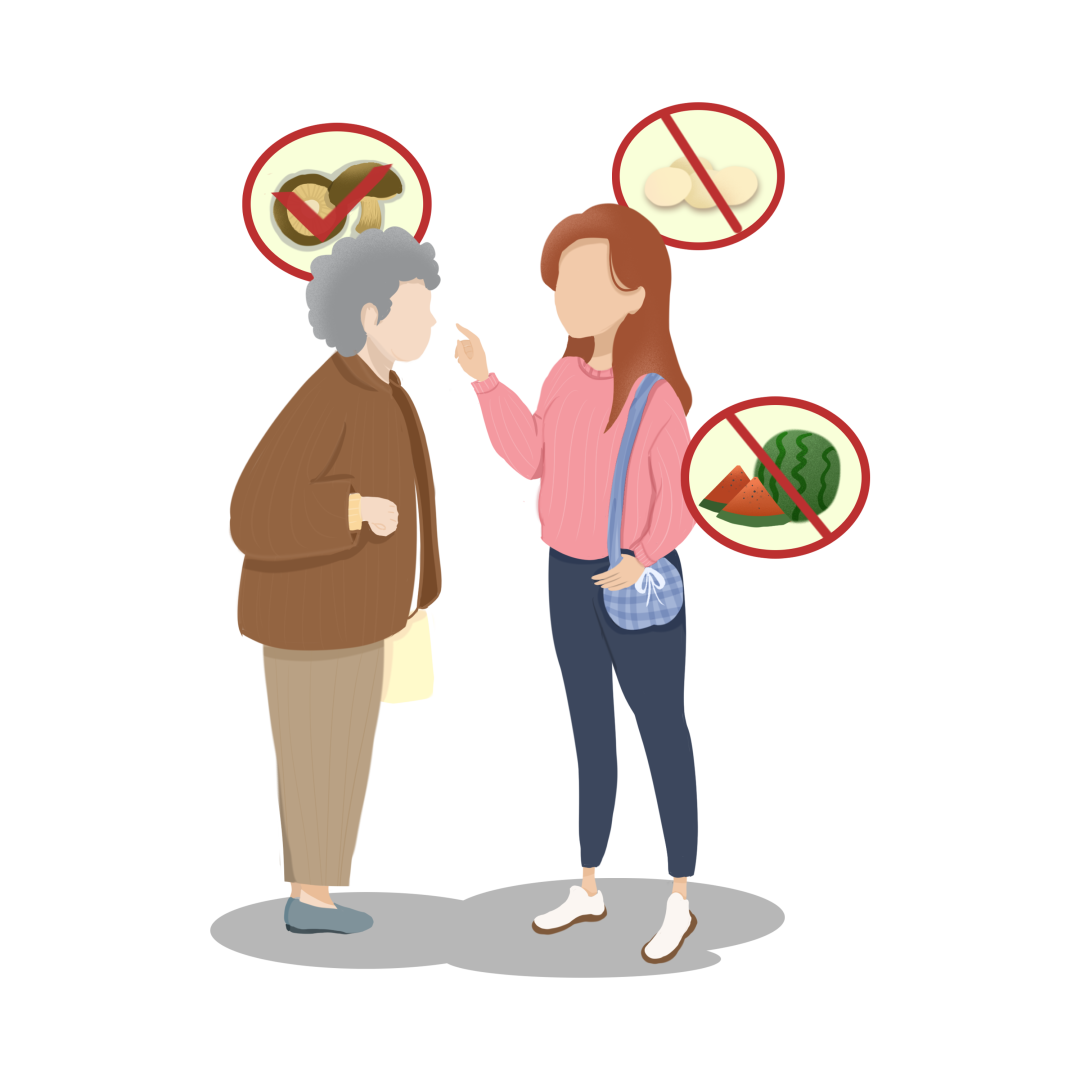

饮食在中医养生中有非常重要的作用,中医强调:“饮食有节,起居有节,不妄作劳”,十分重视饮食调节在保健预防疾病中的作用。

其中,涉及到两个常见问题,一个是人们常说的“发物”,另一个是“忌口”。

因此,针对个体化疾病,结合体质,中医常提出的一些饮食禁忌问题。

#举个例子:有些人吃了西瓜会腹泻,那么西瓜对于他来说就是“发物”,同时素体脾胃虚弱,容易腹泻的患者,也应该避免过多进食寒凉的食物,以免引起身体不适。

有些人吃了虾蟹会出皮疹,那么虾蟹对于他来说就是“发物”。

关于忌口,中医和西医有共同之处。例如:

▶ 疾病属寒证,症见体质虚寒、胃痛喜热、四肢发冷等的患者:应忌食寒凉生冷之食物,如冷饮、西瓜等;

▶ 热证见面目赤红、发热、痔疮下血、失眠心烦者:忌食辛辣刺激之食品,如辣椒、花椒等。

▶ 接受放疗、化疗的患者:常出现口干鼻燥、咽干、舌红少苔、脉细数等阴虚火旺症状,此时忌食辛辣、香燥或油炸食物。

▶ 甜的、油腻的食物,易助湿生痰,舌苔很厚有湿阻的患者应忌食。

▶ 质硬而坚,食之不易消化的食物,对于消化不良胃口差的患者应忌食。